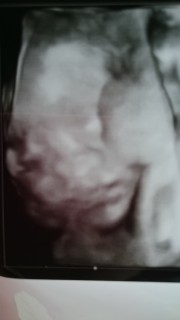

赤ちゃんは24w5dで推定833gで頭、お腹、脚全て1週間分程大きいと言われました!!

頭、お腹、脚全て1週間分程大きく推定体重は839グラム! 特に脚がかなり長い(°_°)♡ 鼻の形と口は旦那似で鼻の高さは私似かな?(^^) 3人目にして初の女の子♡ 旦那に似てガタイのいい子になりそうな予感、、、笑 4Dエコーでは指しゃぶりしたりあくびをしたり、ニコッと笑ったりして可愛かった(o^^o) 上2人ともえくぼがあるのですが、この子にもありそうな感じでした!

初めて顔を見せてくれました。 アメリカと日本のハーフです。 鼻が高くてパパの寝顔に似てる気がする(笑) 可愛い赤ちゃん、早く会いたいな! でももう少しお腹にいてね(^ω^)

赤ちゃんの体重825g。 凄く大きくなってて 元気でした(*⌒▽⌒*) 顔も鼻も口もはっきり分かりました(*⌒▽⌒*) 顔の前に手を伸ばしたり 可愛かったヽ(*´∀`)ノ エコー写真は2枚もらったけど 鼻と口です(笑)

目と鼻は先生がわかりやすくペンで書いてくれました。男の子です。うつ伏せ気味だったので横顔ですが可愛くて可愛くて!旦那さんとメロメロになってます*元気いっぱいに生まれてきてね!楽しみに待ってるよ~^^